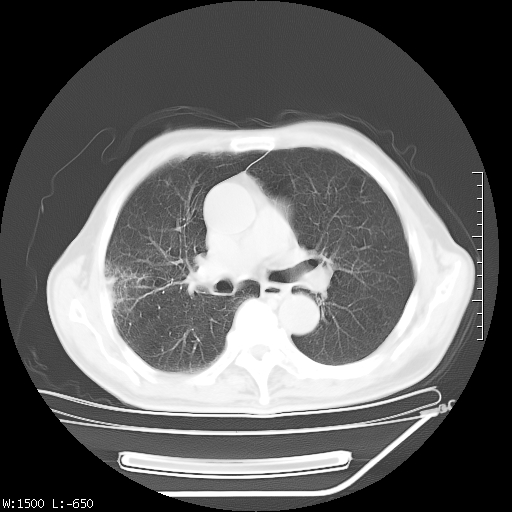

标题: CT23994:男、72、咳嗽、气短两月余,近来消瘦。 [打印本页]

标题: CT23994:男、72、咳嗽、气短两月余,近来消瘦。

右上肺实变,与胸膜关系密切,右肺容积缩小,隆突下淋巴结增大,考虑1 肺结核 2 肺癌

右上肺大片状密度增高影,与胸膜关系密切,内见低密度透亮影,胸膜下可见三角形不张影,左下肺沿支气管走形结节影,纵膈内淋巴结显示。考虑结核并疤痕性不张可能性大,建议穿刺活检,排除肺泡癌。